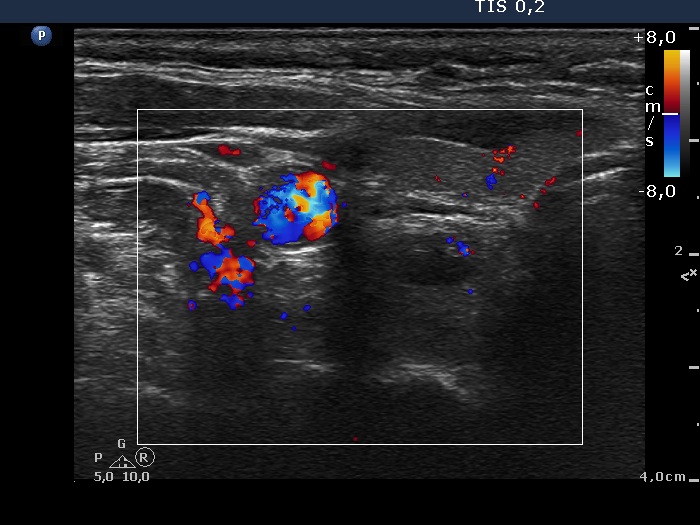

Clinical data: A 63-year-old woman was referred for exact localization of a parathyroid before surgery. The patient had diffuse complaints, including fatigue, depression, weight loss. On routine laboratory blood test, an elevated serum calcium level, thereafter an elevated parathormone level (154 pg/mL) were detected. MIBI scintigraphy disclosed parathyroid adenoma corresponding to the right lower parathyroid.

Ultrasonography. The thyroid was minimally hypoechoic and had several insignificant hypoechoic lesions. There was a solid-cystic mass dorsal to the lower pole of the right lobe.